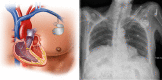

The sinoatrial node (SAN) is the primary pacemaker of the heart. Normal SAN function is crucial in maintaining proper cardiac rhythm and contraction. Sinus node dysfunction (SND) is due to abnormalities within the SAN, which can affect the heartbeat frequency, regularity, and the propagation of electrical pulses through the cardiac conduction system. As a result, SND often increases the risk of cardiac arrhythmias. SND is most commonly seen as a disease of the elderly given the role of degenerative fibrosis as well as other age-dependent changes in its pathogenesis. Despite the prevalence of SND, current treatment is limited to pacemaker implantation, which is associated with substantial medical costs and complications. Emerging evidence has identified various genetic abnormalities that can cause SND, shedding light on the molecular underpinnings of SND. Identification of these molecular mechanisms and pathways implicated in the pathogenesis of SND is hoped to identify novel therapeutic targets for the development of more effective therapies for this disease. In this review article, we examine the anatomy of the SAN and the pathophysiology and epidemiology of SND. We then discuss in detail the most common genetic mutations correlated with SND and provide our perspectives on future research and therapeutic opportunities in this field.